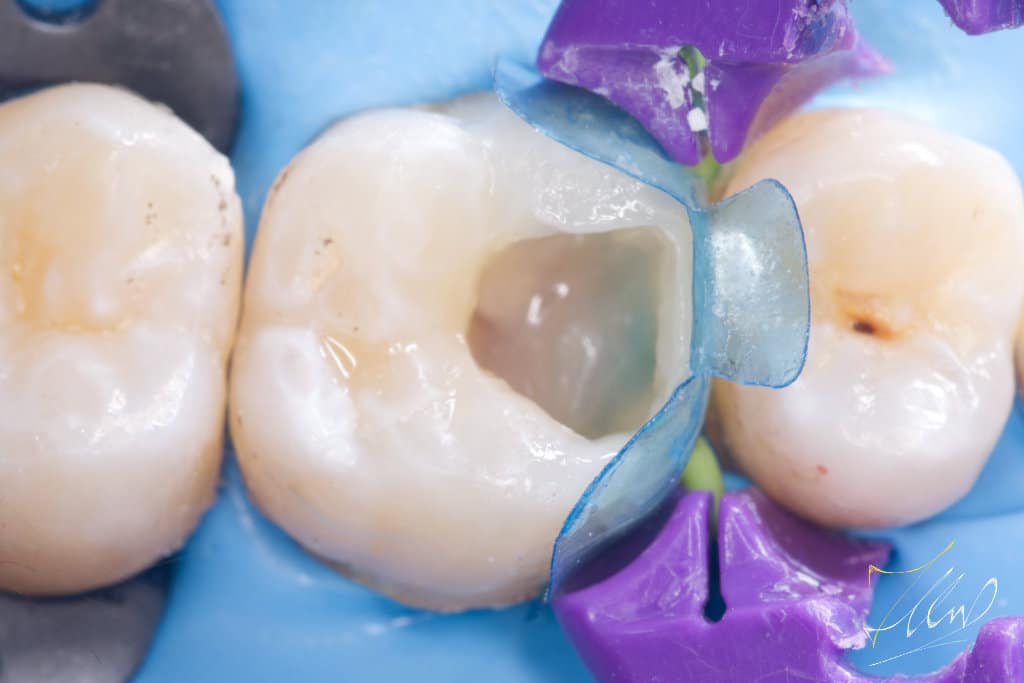

To facilitate matrix placement and achieve optimal contact and contour, it is essential to restore the buccal wall to its original shape.By marking the lost structure and build the buccal cusp to enhance the structure, consider reinforcing the buccal cusp with composite material and then inserting FRC (ever x) to effectively manage the separation force of the ring without compromising the integrity of the composite.

The blue bio fit matrix was chosen .Together with anatomical deep caries wedge to get the optimal fit.